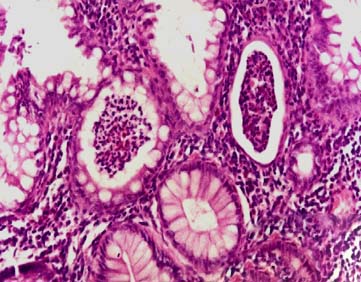

皮肤活检多无特异性改变。可见皮肤角层下水疱,再棘细胞增厚、水肿,血管周围可见中性多形核和嗜酸细胞浸润。